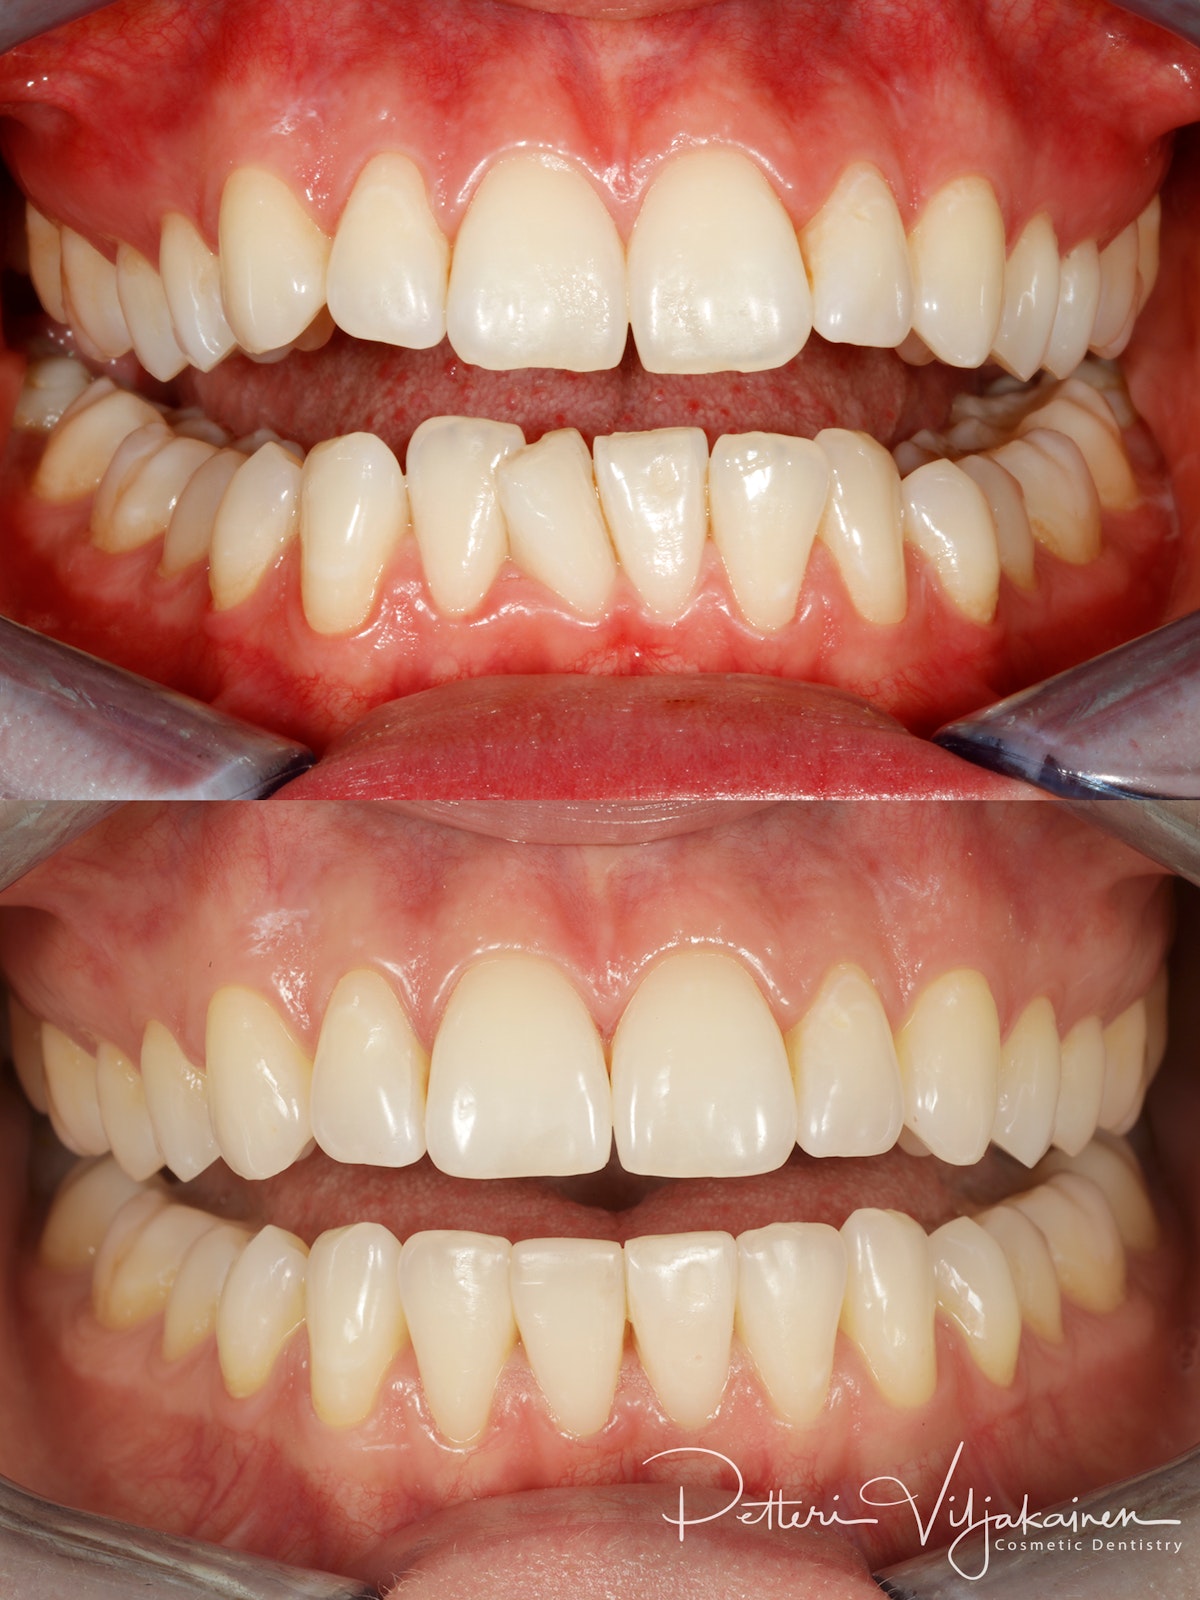

10 kk hoito (Comprehensive). Aavistus esteettistä muovia lisätty yläkulmahampaisiin hoidon jälkeen.